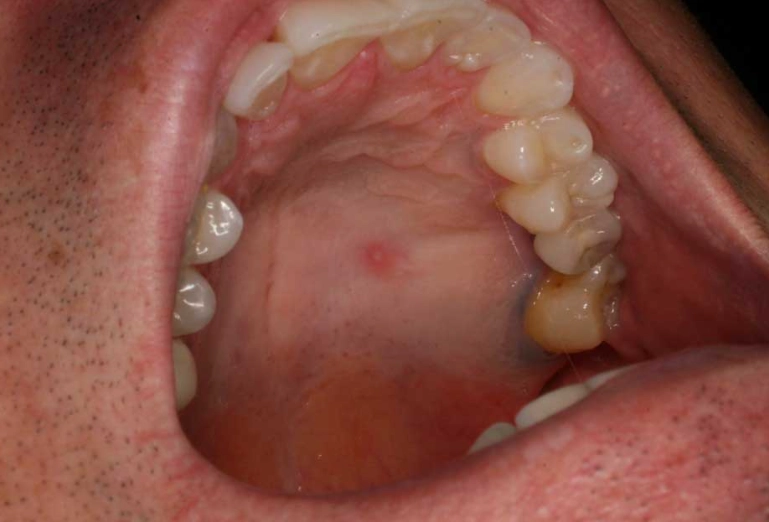

Q: Is it normal to have lumps on the roof of your mouth?

A: The roof of the mouth (palate) has specific structures. A bony, hard lump in the midline could be a torus palatinus, a harmless bony growth. A soft lump could be a variety of things, from a minor salivary gland issue to something else. Any new, persistent lump on the palate should be checked by a dentist.